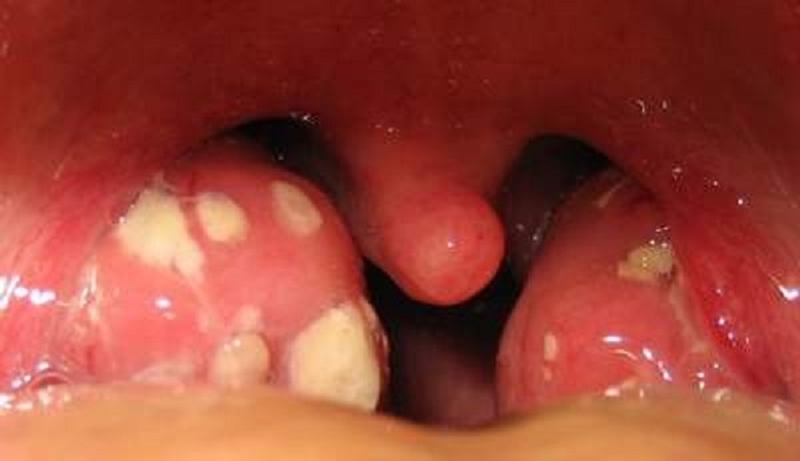

Hình ảnh viêm amidan liên cầu khuẩn

Khi bệnh do liên cầu khuẩn gây ra, bạn quan sát họng sẽ thấy amidan bị sưng đỏ, có mủ trắng bẩn. Ở trẻ nhỏ thì có thể xuất hiện màng xám hoặc trắng ở amidan. Kèm theo là các triệu chứng khác như: